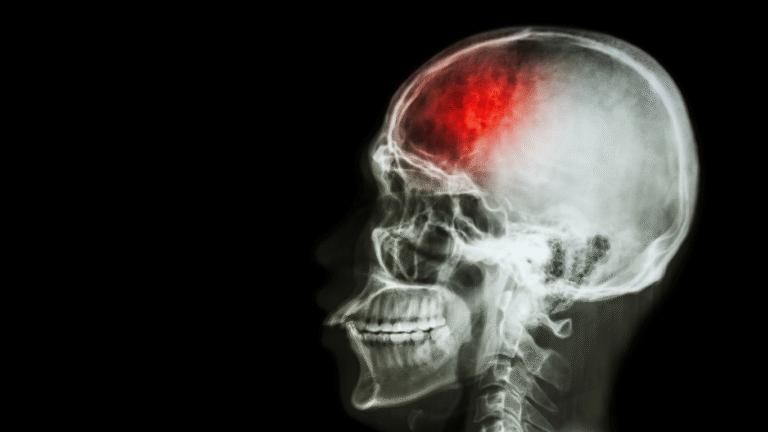

Os meningiomas são os tumores cerebrais benignos mais comuns. Eles podem crescer lentamente e causar prejuízos importantes ao comprimir estruturas adjacentes do cérebro. Entender os sinais, o diagnóstico e as

A descoberta de um tumor cerebral é sempre um momento de apreensão, mesmo quando o diagnóstico aponta para um tumor benigno. Apesar de não apresentarem comportamento agressivo como os tumores